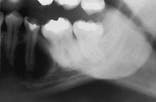

Hypercementosis

2. Identify the radiographic appearance of hypercementosis:

3. Identify the treatment for hypercementosis:

4. Identify which of the following is associated with hypercementosis: